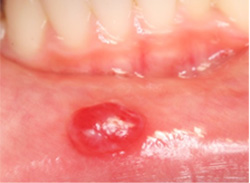

アフター性口内炎

- [好発年齢・性差]

- 特にない

- [好発部位]

- 舌、頬粘膜、上下口唇粘膜、口蓋歯肉、歯肉頬移行部の順に好発する。

再発性アフタの場合は1〜3ヶ月周期で起こることが多い。 - [症状]

- 周りが赤く輪郭の明瞭な小さな円形の口内炎で、痛みが強い。発熱などがみられる場合と、全身症状はなく口内炎だけがみられる場合もある。原因は不明。食物アレルギーやビタミンの欠乏、ストレス、咬傷などが誘因となる。

- [治療]

- 強い痛みへの対症療法が中心となる。口腔内の洗浄と消毒を行い、場合によっては抗菌薬入り軟膏や副腎皮質ステロイド軟膏を処方する。